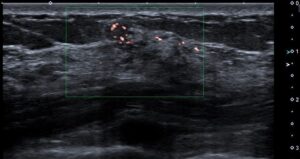

…?と思いカラードプラをあててみると、

血流シグナルがある…